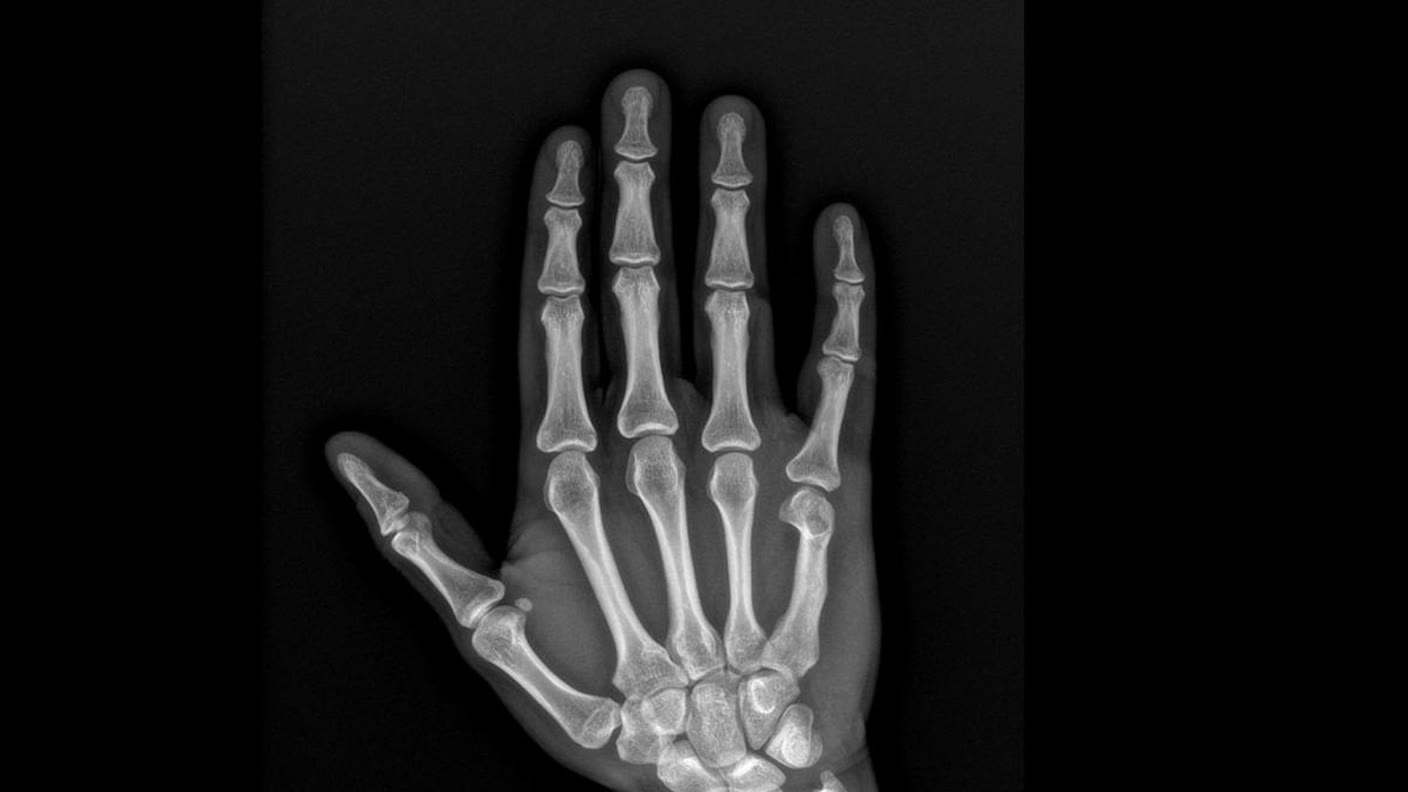

Alle erforderlichen Röntgenaufnahmen können bei uns sofort durchgeführt werden. Die digitale Röntgentechnik liefert sehr gute Bildqualität, schnelle Verfügbarkeit und klare Grundlagen für die weitere Diagnose und Behandlung.

Digitales Röntgen ist besonders hilfreich, wenn Knochen, Gelenke oder die Stellung einzelner Strukturen rasch beurteilt werden müssen. So kann direkt entschieden werden, ob eine konservative Behandlung ausreicht oder ob weitere Bildgebung wie MRI oder CT sinnvoll ist.